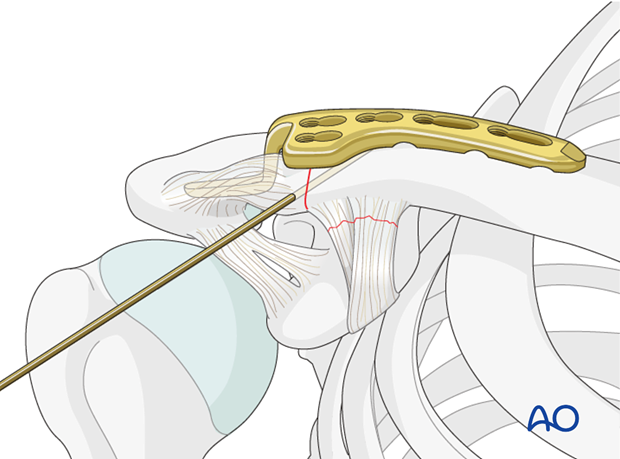

Open Reduction and Internal Fixation (ORIF)

This is the most common surgical method.

Procedure steps:

- Small incision over the collarbone

- Bone fragments repositioned

- Fixation using metal plate and screws

This stabilizes the bone and allows early functional recovery.